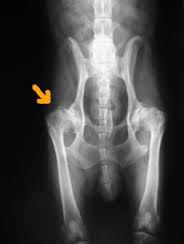

Een ervaren dierenarts kan bij een pup van 8 weken voelen of het heupgewricht stabiel is. Wanneer de groei en beweging dan in goede banen wordt geleid zal een dergelijke pup ook minder snel HD ontwikkelen. Het heeft dus te maken met de stabiliteit van het heupgewricht. Bij een hond die verdacht wordt van HD wordt eerst een uitgebreid algemeen onderzoek uitgevoerd. De achterhand wordt gestrekt en gebogen, waarbij de dierenarts let op pijn bij het strekken en de spierspanning. Vervolgens wordt er een röntgenfoto gemaakt. Hiermee kan bevestiging of uitsluitsel van HD worden gegeven.

ED is een afkorting voor elleboogdysplasie. HD is een afkorting van heupdysplasie. Het is een vervorming van de heup waarbij de kom en de kop niet meer goed op elkaar passen. De afwijking doet zich voor bij jonge opgroeiende honden waarbij de groei niet optimaal verloopt en er zo een afwijking ontstaat. Door deze afwijking kan er op den duur artrose ontstaan. Het komt voornamelijk bij grote honden voor, maar wordt ook steeds vaker bij kleine honden gezien.